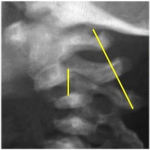

INSTRUCCIÓN ORTOPÉDICA DE POSGRADO – IMÁGENES

Presentación del caso

Pedro L. Bazán, Arles Pérez Gutiérrez, Alin L. Garay

Resolución del caso